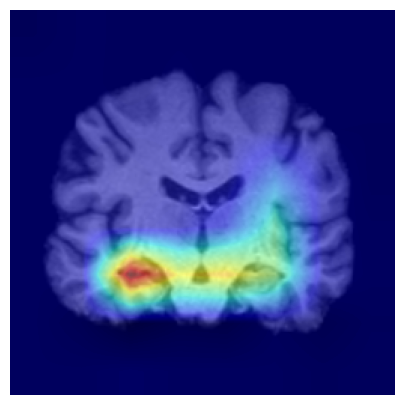

4.3.2 ADNI

We consider two groups constructed from the ADNI dataset based on hippocampal volume, a well-established neuroimaging biomarker of Alzheimer’s disease–related neurodegeneration. Each group includes 918 2D slices. Subjects exhibiting reduced hippocampal volume indicative of hippocampal atrophy are assigned to Group 1, while subjects with preserved hippocampal volume form Group 2. This stratification induces group differences associated with disease-relevant anatomical variation and provides a clinically meaningful setting for evaluating whether the proposed feature-level explanations highlight brain regions known to be implicated in Alzheimer’s disease/cognitive impairment.

We use a ResNet-50 encoder pretrained on the UK Biobank dataset, predicting the age of brains, and adapt this pretrained model using a linear probing strategy on the ADNI dataset. Specifically, we train a logistic regression layer on top of the frozen encoder to predict group membership, while keeping all encoder parameters fixed. After training, the linear head is discarded, and the frozen encoder is used to extract embeddings for two-sample testing and for generating feature-level explanations. We apply the proposed feature-level explanation method to individual MRI scans and assess whether the resulting attributions align with known disease-related neuroanatomical patterns.

To assess the robustness of our feature-level explanations, we apply multiple channel-aggregation strategies to the gradients of the test statistic: (i) gradient-weighted aggregation Selvaraju et al. (2017), (ii) second-order gradient aggregation Chattopadhay et al. (2018), and (iii) layer-wise spatial aggregation Jiang et al. (2021). Across all variants, the resulting heatmaps remain consistent. Additional details are provided in the Supplementary Material.

Results.

Figure 7 indicates the qualitative results. Our explainability method consistently highlights the hippocampal and medial temporal lobe regions, and the resulting heatmaps show strong correspondence with areas affected by hippocampal atrophy. These results supports that the identified regions align with established AD biomarkers.